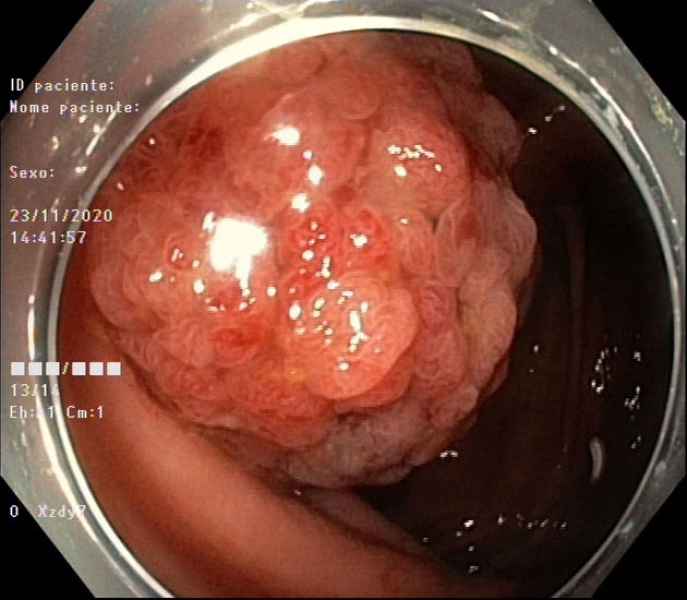

Hybrid endoscopic full-thickness resection of an appendicular laterally spreading tumour

Fotografia